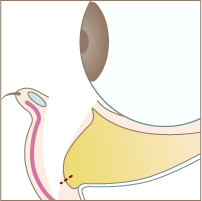

Step 01

まつ毛の下の赤い点線部分を切開します。